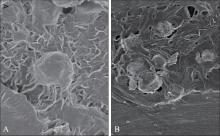

目的 探究负载了血小板浓缩生长因子(CGF)的聚己内酯(PCL)—聚乙二醇(PEG)支架对人牙周膜干细胞(hPDLSCs)黏附、增殖及成骨分化能力的影响。 方法 通过浸入及冻干法制备PCL-PEG-CGF复合支架,观察复合支架的显微结构并检测其机械性能及生物相容性。酶消化法培养hPDLSCs,并通过流式细胞术鉴定hPDLSCs。选取第三代hPDLSCs,分别通过CCK-8实验、4’,6-二脒基-2-苯基吲哚(DAPI)染色、碱性磷酸酶(ALP)染色、茜素红染色及Western blot实验检测PCL-PEG-CGF复合支架对hPDLSCs黏附、增殖及成骨分化能力的影响及成骨相关蛋白[Runt相关转录因子2(Runx2)、ALP、骨形态发生蛋白2(BMP2)]的表达情况。 结果 PCL-PEG-CGF复合支架在扫描电镜下呈孔隙大小不等的蜂窝状结构,其亲水性6 s时θ角接近0°,弹性模量为(4.590 0±0.149 3)MPa,其亲水性、断裂拉伸强度及断裂延伸率均与PCL-PEG支架相似;hPDLSCs在PCL-PEG-CGF复合支架上的黏附能力明显优于PCL-PEG支架(P<0.01),与对照组相比,第3、5、7天时各实验组的hPDLSCs增殖速率显著增加(P<0.01),且PCL-PEG-CGF复合支架与其余组间差异有统计学意义(P<0.01);PCL-PEG-CGF复合支架组ALP活性明显升高(P<0.05),矿化结节数量明显增加及成骨相关蛋白(Runx2、BMP2、ALP)的表达均明显增强(P<0.05)。 结论 PCL-PEG-CGF复合支架具有较好的机械性能及生物相容性,可促进hPDLSCs黏附及增殖,并通过增强成骨相关蛋白的表达促进hPDLSCs的成骨分化能力。

Objective This study investigated the effects of a polycaprolactone (PCL)-polyethylene glycol (PEG) scaffold incorporated with concentrated growth factor (CGF) on the adhesion, proliferation, and osteogenic differentiation of human periodontal ligament stem cells (hPDLSCs). Methods The PCL-PEG-CGF composite scaffold was fabricated using an immersion and freeze-drying technique. Its microstructure, mechanical properties, and biocompatibility were systematically characterized. The hPDLSCs were isolated through enzymatic digestion, and the hPDLSCs were identified through flow cytometry. Third-passage hPDLSCs were seeded onto the composite scaffolds, and their adhesion, proliferation and osteogenic differentiation were assessed using CCK-8 assays, 4’,6-diamidino-2-phenylindole (DAPI) staining, alkaline phosphatase (ALP) staining, alizarin red staining, and Western blot analysis of osteogenesis-related proteins [Runt-related transcription factor 2 (Runx2), ALP, and morphogenetic protein 2 (BMP2)]. Results Scanning electron microscopy revealed that the PCL-PEG-CGF composite scaffold exhibited a honeycomb-like structure with heterogeneous pore sizes. The composite scaffold exhibited excellent hydrophilicity, as evidenced by a contact angle (θ) approaching 0° within 6 s. Its elastic modulus was measured at (4.590 0±0.149 3) MPa, with comparable hydrophilicity, fracture tensile strength, and fracture elongation to PCL-PEG scaffold. The hPDLSCs exhibited significantly improved adhesion to the PCL-PEG-CGF composite scaffold compared with the PCL-PEG scaffold (P<0.01). Additionally, cell proliferation was markedly improved in all the experimental groups on days 3, 5, and 7 (P<0.01), and statistically significant differences were found between the PCL-PEG-CGF group and other groups (P<0.01). The PCL-PEG-CGF group showed significantly elevated ALP activity (P<0.05), increased mineralization nodule formation, and upregulated expression of osteogenic-related proteins (Runx2, BMP2 and ALP; P<0.05). Conclusion The PCL-PEG-CGF composite scaffold exhibited excellent mechanical properties and biocompatibility, enhancing the adhesion and proliferation of hPDLSCs and promoting their osteogenic differentiation by upregulating osteogenic-related proteins.